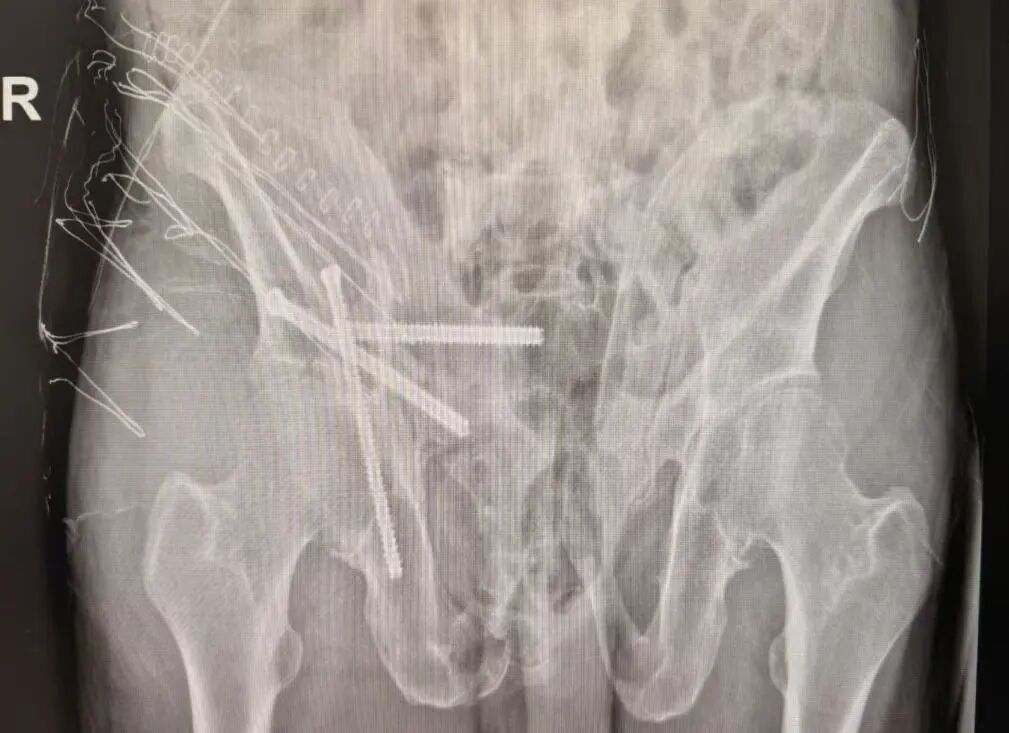

术后

术后患者恢复迅速,第二天已能下床站立。整个过程真正做到了“快、准、稳”,极大提升了手术安全性与疗效可控性。